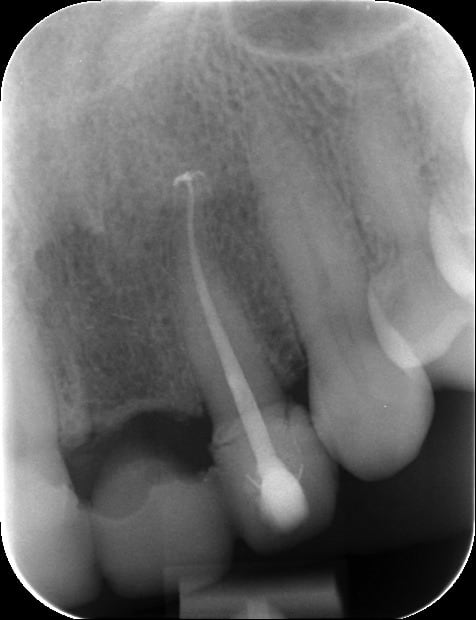

10/07/2012 à 23h01

Je déterre mon poste en mettant les photos du cas. Désolé il manque le principal: la photo de l'état initial...

Donc par précaution, j'ai choisi de faire l'endo sur la 22, suite au coiffage direct (même si la dent était asymptotique pour la patiente).

Je n'ai pas osé faire que de l'Emax. J'ai décidé avec le labo de faire une armature Zircone avec de l'Emax pressée dessus.

Il y a les photos du biscuit, du bridge fini le jour de la pose et à 3 semaines.

A vos critiques, merci!

10/07/2012 à 23h39

C'est très beau.

Et belle endo aussi :-)